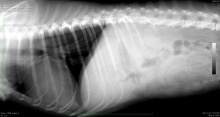

そこで、念のためにレントゲンを撮影してみましたが、レントゲンには大きな異常は認められませんでした。